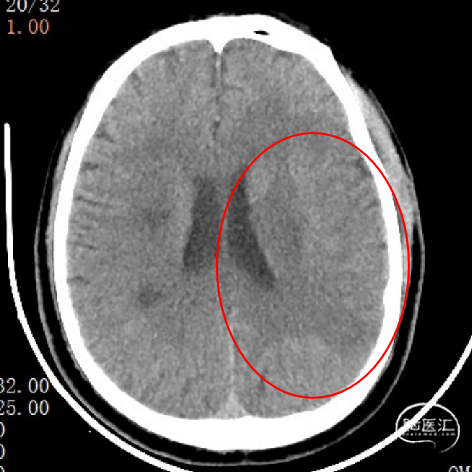

CT

rCBF<30%:25.1ml

Tmax>6.0s:173.9ml

失配体积:148.8ml

1、急性脑梗死。2、左侧大脑中动脉M1段闭塞。